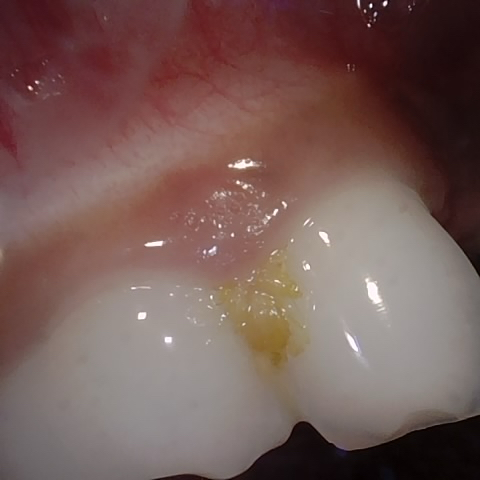

Annotated as "Bad"